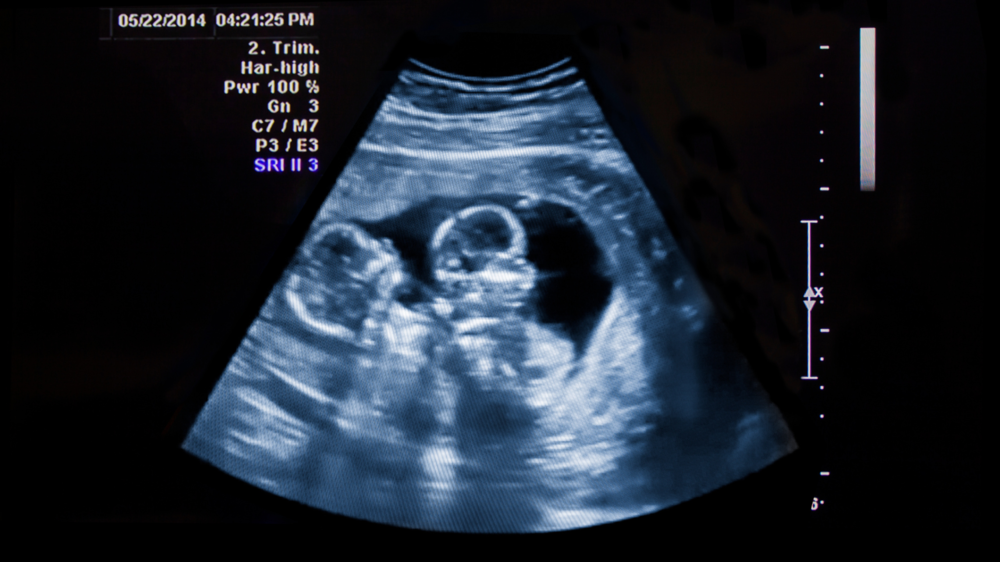

Twin-to-Twin Transfusion Syndrome (TTTS) is a rare condition affecting identical twins sharing one placenta. TTTS happens when blood flow between the twins becomes uneven. This causes one twin to receive too little and the other too much blood. Early diagnosis, monitoring, and treatment are essential to protect both babies.

The news of being pregnant with twins doubles the excitement and happiness. But twin pregnancies can have their challenges too. Twin-to-Twin Transfusion Syndrome (TTTS) is one such rare challenge of twin pregnancy. This is a rare complication that affects identical twins sharing one placenta. It occurs when blood flow between the twins becomes unbalanced, causing one baby to get too little and the other too much.

Twin-to-Twin Transfusion Syndrome (TTTS) is a rare pregnancy complication affecting identical twins who share a single placenta. These twins are called monochorionic twins. In normal instances, identical twins sharing the same placenta equally share blood and nutrients. However, this is not the case with twins having TTTS.